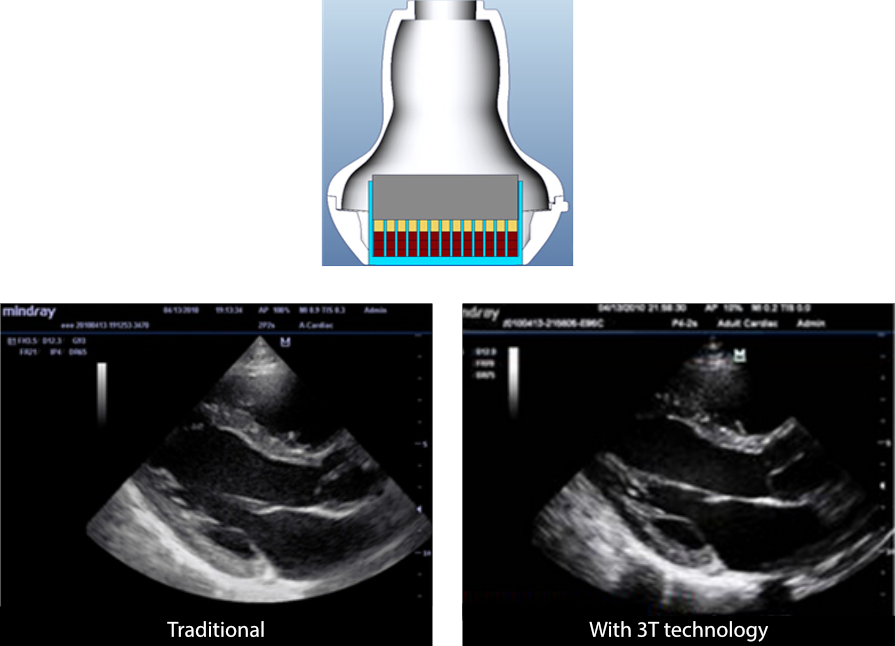

3T Transducer Technology?

Tecnolog├Ła patentada de transducci├│n de Mindray para aumentar el ancho de banda de la imagen, as├Ł como la eficiencia de transmisi├│n.

┬Ę Dise?o de triple capa coincidente para una mayor sensibilidad, ancho de banda m├Īs amplio y S/R mejorado

┬Ę Dise?o de corte total para reducir el ruido diaf├│nico y mejorar la directividad y la resoluci├│n lateral

┬Ę Dise?o con regulaci├│n t├®rmica para una mejor transmisi├│n ac├║stica